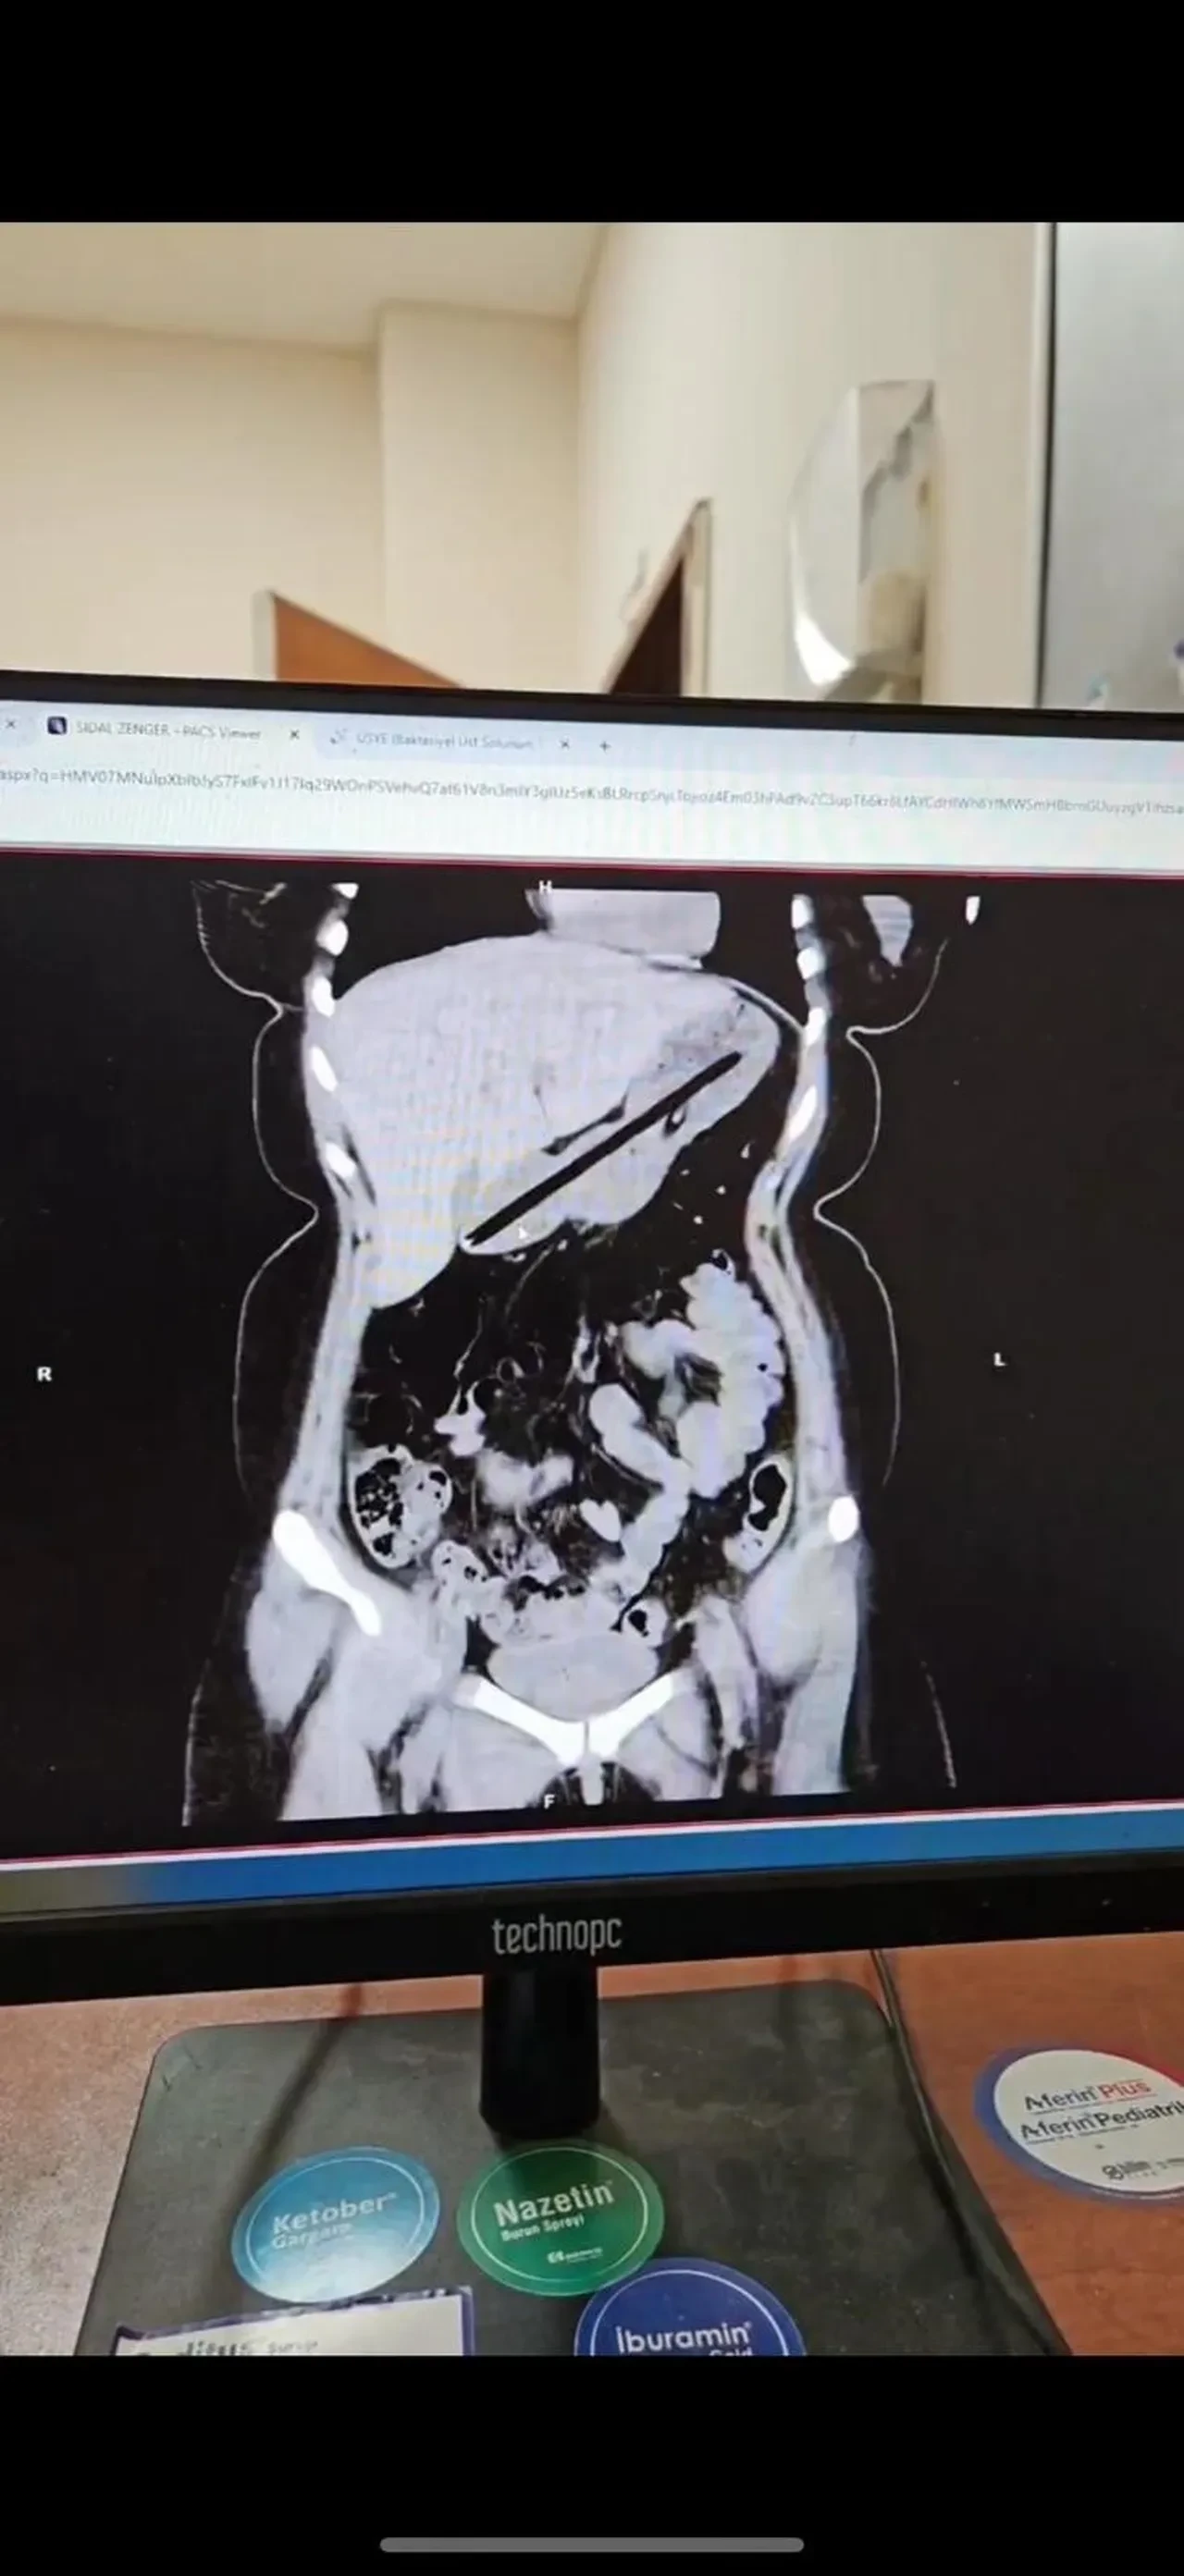

Operasyonu gerçekleştiren Dr. Öğretim Üyesi Adem Aslan, ilk kez böyle bir vakayla karşılaştıklarını belirterek, "22 yaşındaki bayan hastamız kalem yutma şikayetiyle ilçe devlet hastanemize başvurmuştu. Tomografisinde midesinde yabancı cisim olduğu görüldü. Biz de tetkiklerimizde midesinde kalem olduğunu gözlemledik. Daha önce toplu iğne, kemik parçası gibi yabancı cisimlerle karşılaşıyorduk ama bu kadar uzun ve ince bir cisim ilk kez karşımıza çıktı. Midenin boşalması için bir gün bekledik ve ertesi gün yaptığımız endoskopide hastanın bir değil iki kalem yuttuğunu gördük. Yaklaşık bir buçuk saat süren işlemde kalemleri endoskopik yöntemle çıkardık. Hastamızın Obsesif Kompulsif Bozukluğu olduğu için ailesine yalnız bırakmamalarını ve bu tür cisimleri ortalıkta bulundurmamalarını tembih ettik. Bir gün müşahede altında tuttuktan sonra şifa ile taburcu ettik" dedi.